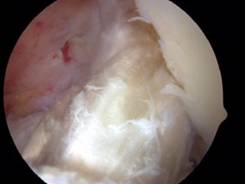

常规开展膝、肩、踝、肘关节镜手术,治疗:膝关节半月板损伤、交叉韧带损伤、慢性滑膜炎、冻结肩(肩周炎)、钙化性肌腱炎、肩袖损伤、肩关节撞击征、复发性肩关节脱位等。

肩关节镜手术 肩袖损伤修复术前

膝关节镜下前交叉韧带重建术 肩袖损伤修复术后